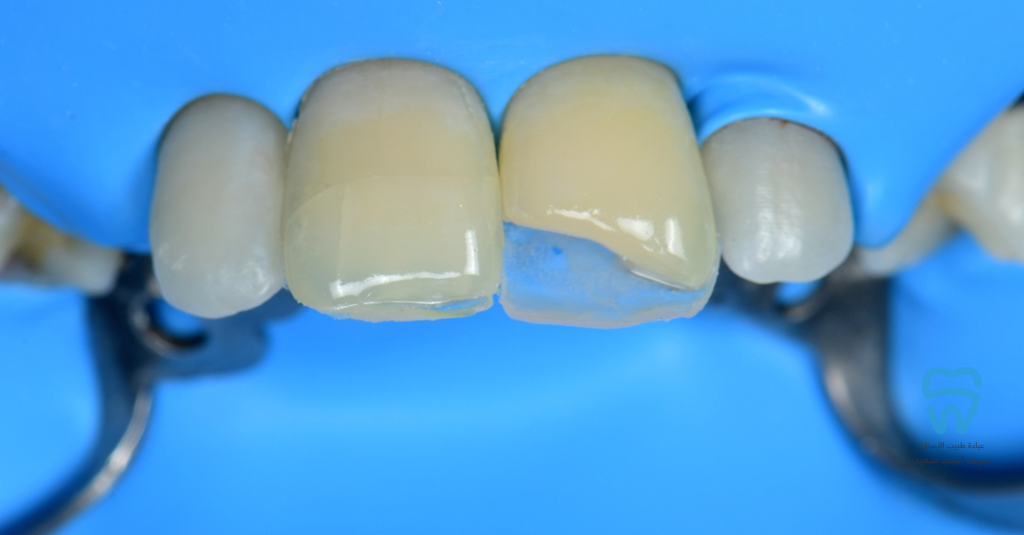

Isolation and cavity preparation

Enamel shade palatal shell

3D layering